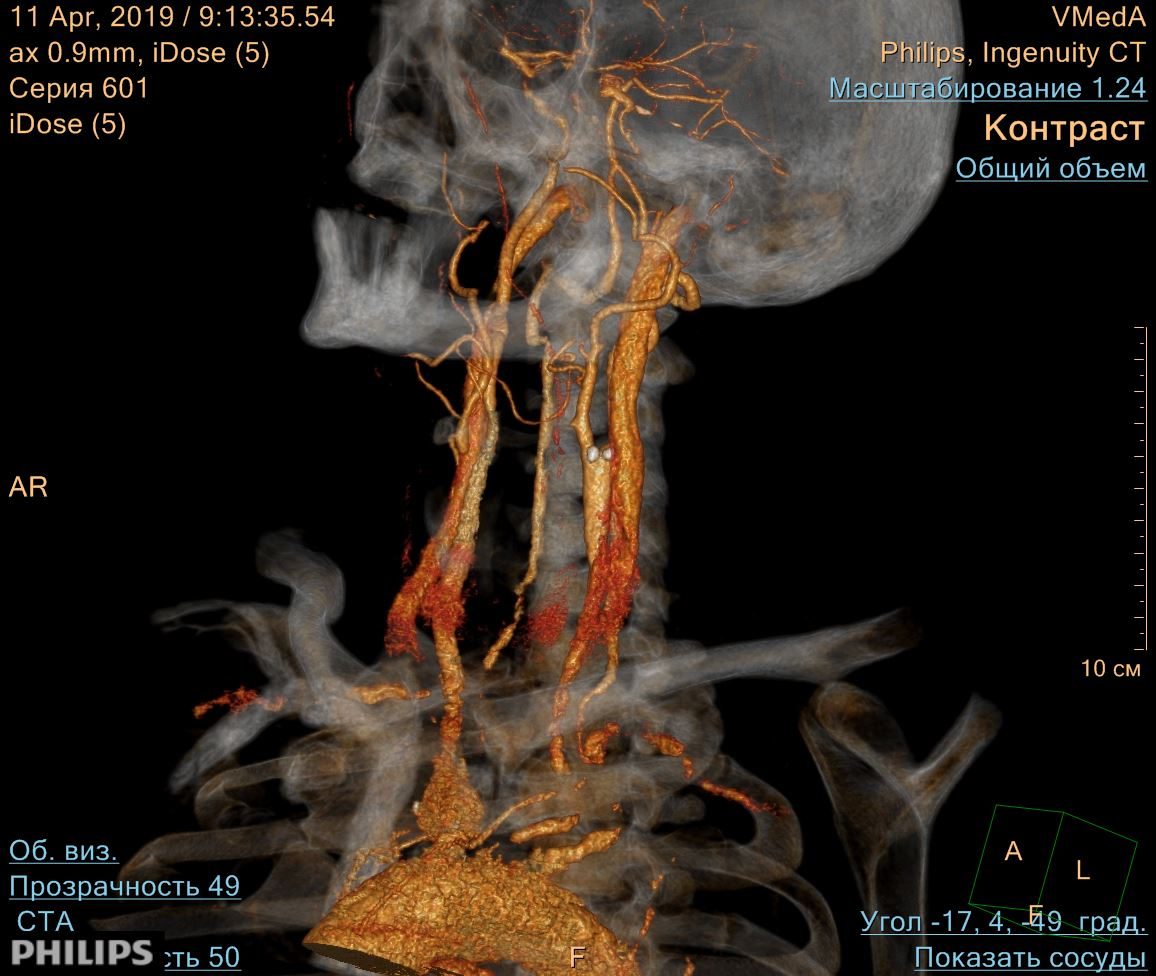

Результаты КТ-ангиографии: протяженная окклюзия левой внутренней сонной артерии, стеноз правой внутренней сонной артерии в приустьевом отделе на 40% по диаметру по ECST и на 20% по диаметру по NASCET.

Рис. 2. КТ-ангиография сосудов головы и шеи, 3D реконструкция. Окклюзия левой внутренней сонной артерии в приустьевом отделе.